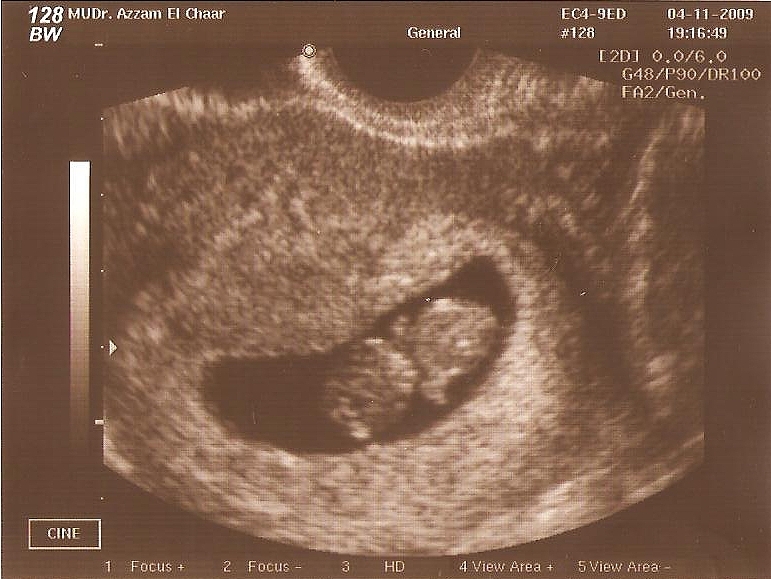

02-9+4tt 2,6cm